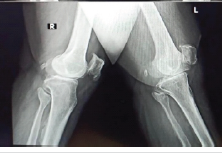

Non-union Hoffa’s fracture in an Adult Male managed with Total Knee Arthroplasty : A Rare Case Report